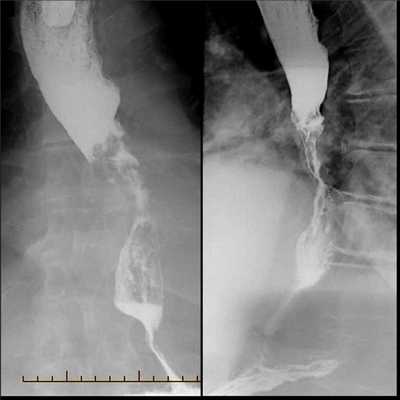

Рентгенологическое исследование пищевода, желудка и двенадцатиперстной кишки с контрастным веществом (сульфатом бария) имитирует прием человеком пищи, при этом за счет приема через рот контрастного вещества «прокрашиваются» измененные участки пищевода. Исследование позволяет наглядно оценить локализацию и протяженность опухолевого поражения органа и степень сужения его просвета.

- Рентгенография с бариевым контрастом. Пациент принимает внутрь сульфат бария, который обволакивает стенки пищевода. Это позволяет увидеть на снимке рельеф стенок и обнаружить сужение просвета. На ранней стадии рак может иметь вид небольших круглых выпуклостей, то есть бляшек. На поздней стадии развития новообразование принимает вид большой опухоли неправильной формы, которая может вызывать сильное сужение пищевода. Рентгенография также позволяет диагностировать трахеопищеводную фистулу, то есть когда из-за разрушения новообразованием стенки пищевода на всю толщину пищевод начинает сообщаться с трахеей.

Рентгенодиагностика рака пищевода